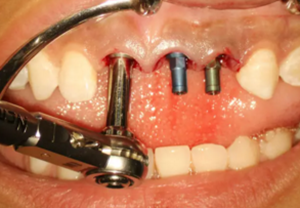

(2)即刻種植、即刻臨時修復(fù)。術(shù)中不翻瓣微創(chuàng)拔除牙根,牙槽 窩骨壁完整。在多級導(dǎo)板輔助下完成種植窩洞制備,植入Bego柱形種植 體,型號分別為:上頜右側(cè)中切牙位點4.1mm×15mm、上頜左側(cè)中切牙 位點?3.75mm×15mm、上頜左側(cè)側(cè)切牙位點3.25mm×15mm,扭矩均為 35N·cm。種植體與唇側(cè)骨壁間隙約2mm,植入Bio-Oss®Collagen骨膠 原。戴入橋用鈦臨時基臺,臨時冠就位順利,自凝樹脂口內(nèi)粘接后適當(dāng)修整 外形,充分磨光,調(diào) 至正中 、前伸 和側(cè)方 與對頜牙均無接觸。術(shù)后 根尖片顯示種植體位置、方向良好。

圖8 導(dǎo)板輔助下備洞

圖9 植入種植體

圖10 植入骨膠原

圖11 戴入臨時修復(fù)體

圖12 即刻修復(fù)完成

圖13 術(shù)后即刻根尖片